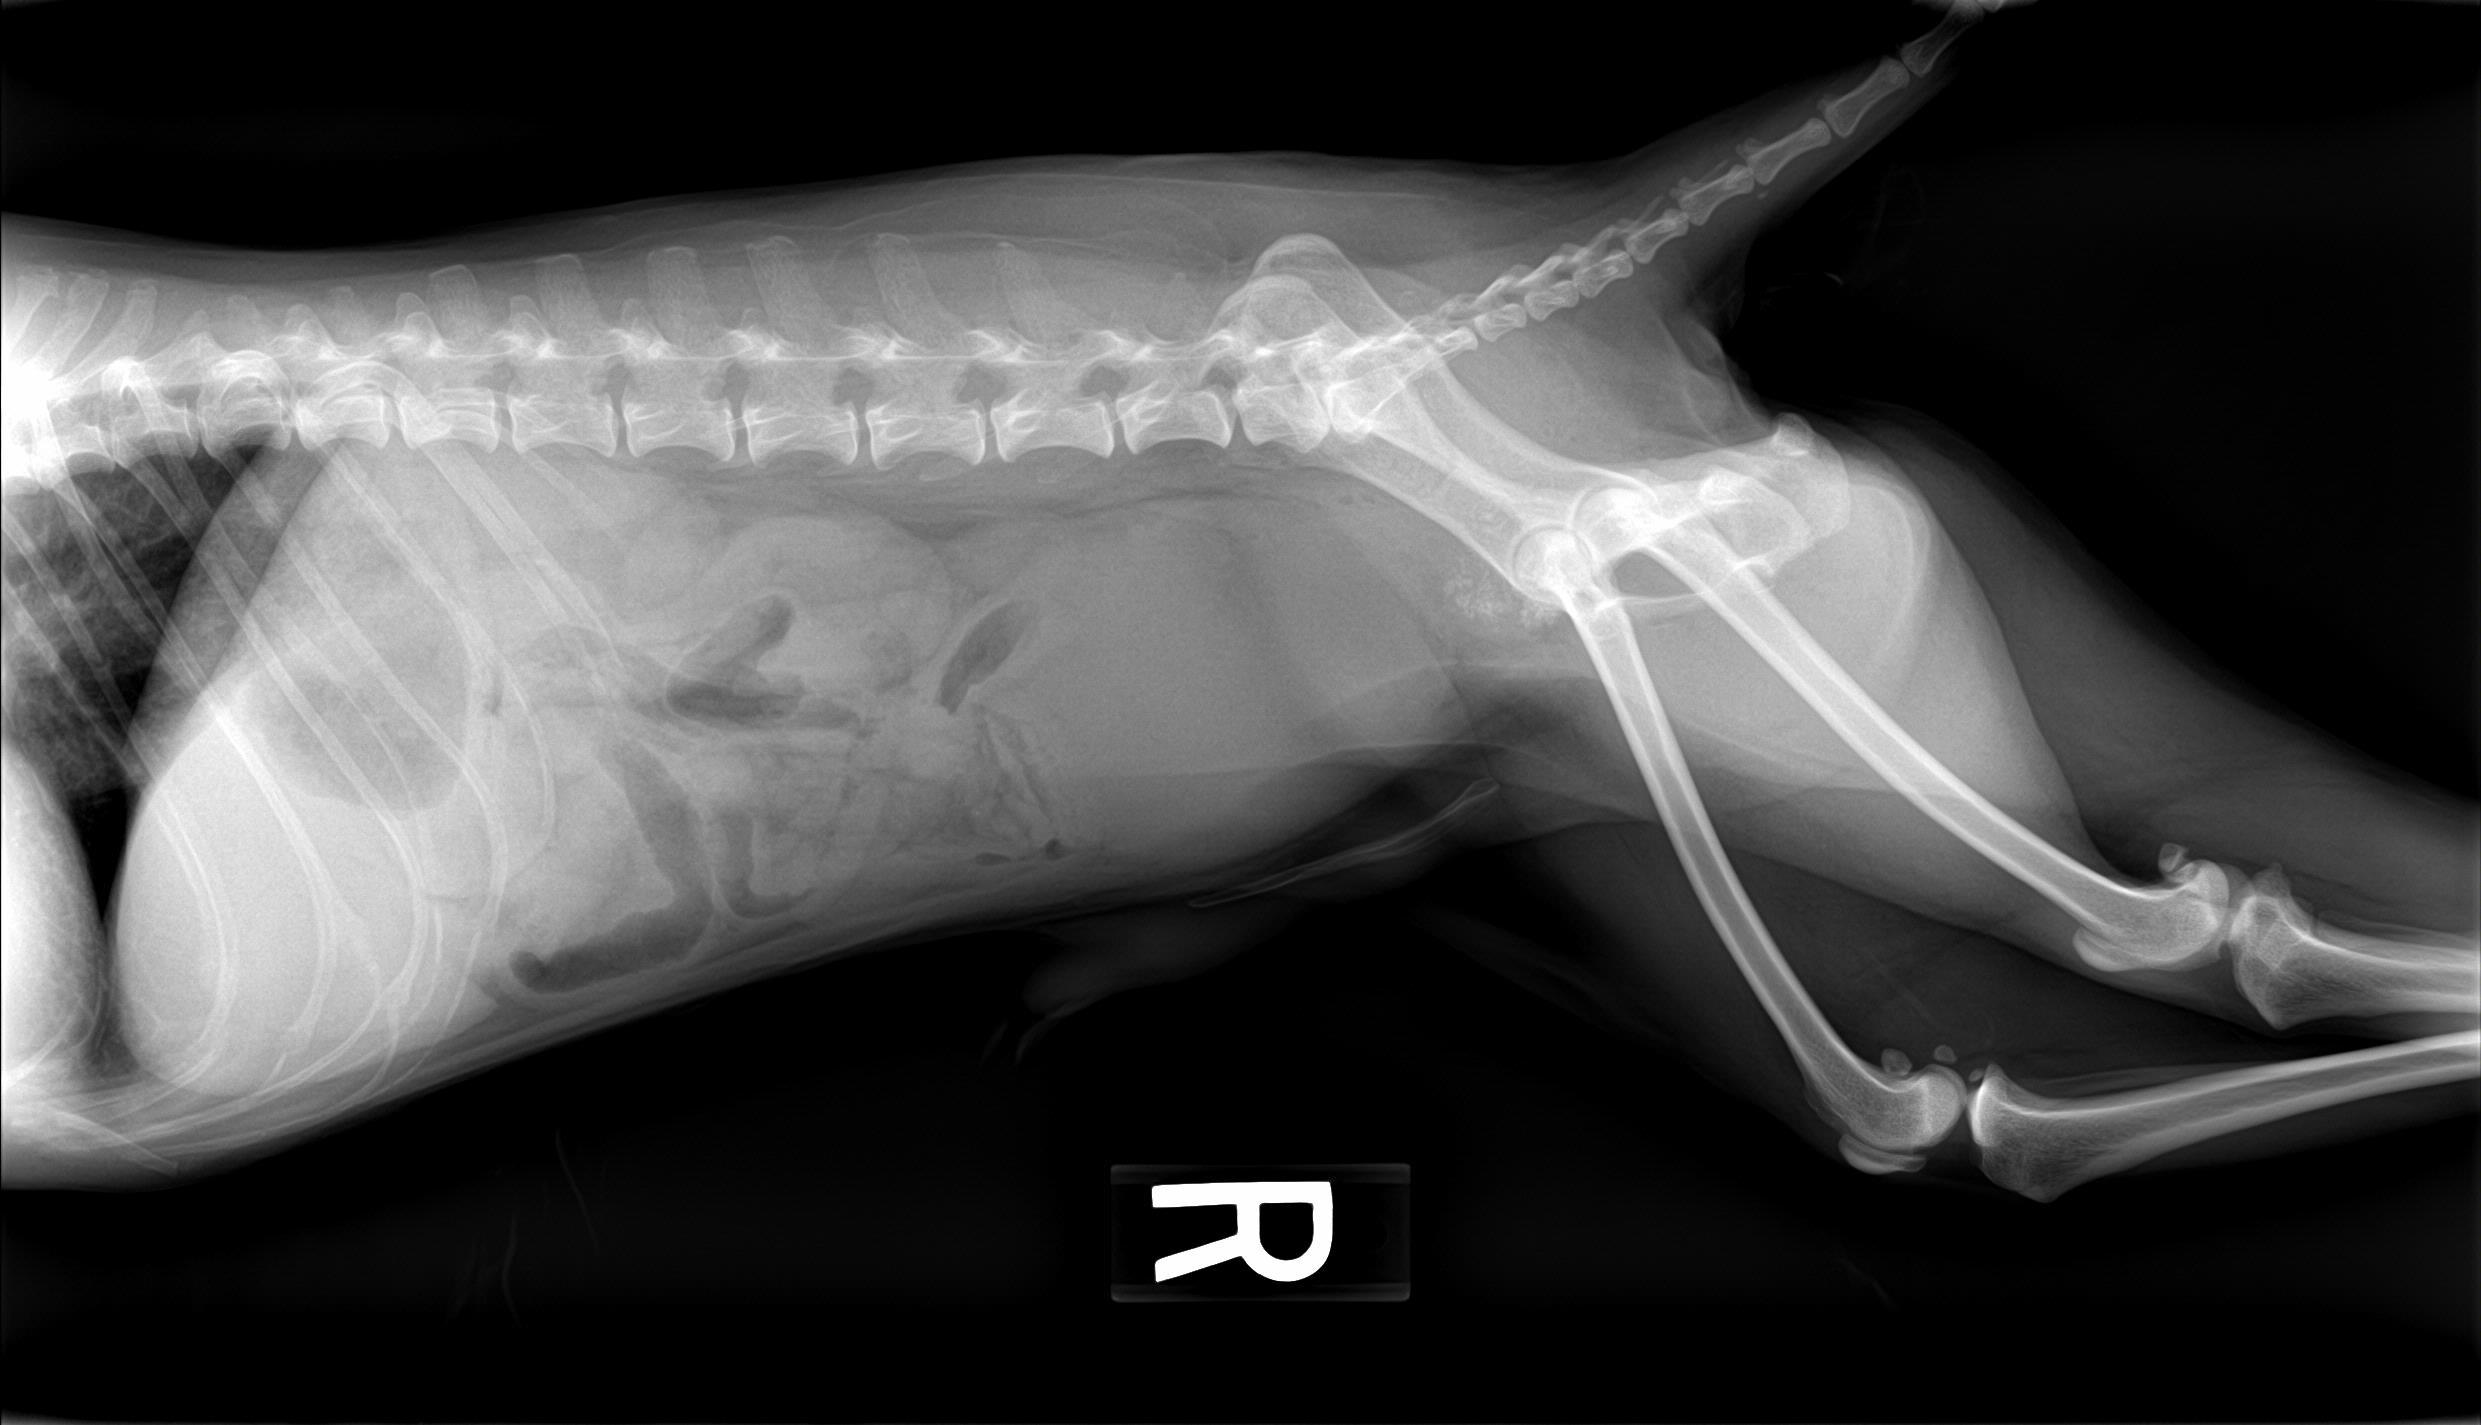

A 14-year-old neutered male Pomeranian dog was presented for evaluation of pollakiuria, diarrhea, inappetence, and lethargy. Abnormalities on physical examination included a painful, enlarged and symmetrical prostate, a very large and firm urinary bladder that could be expressed, and a grade III/VI heart murmur. On survey thoracic radiographs, calcification of the prostate gland was evident.

A 14-year-old neutered male Pomeranian dog was presented for evaluation of pollakiuria, diarrhea, inappetence, and lethargy. Abnormalities on physical examination included a painful, enlarged and symmetrical prostate, a very large and firm urinary bladder that could be expressed, and a grade III/VI heart murmur. On survey thoracic radiographs, calcification of the prostate gland was evident.